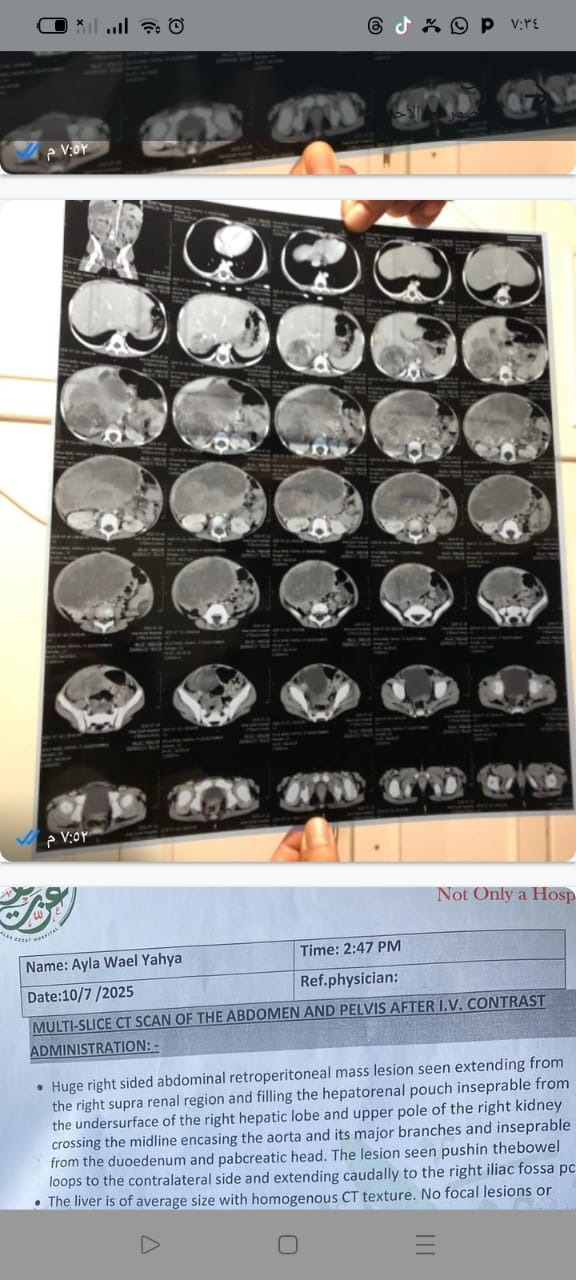

My name is Amin Hussein, and I am reaching out on behalf of a precious little girl named Ayla Yahya, who is living in Egypt. Ayla is a sweet and bright young child whose life has been turned upside down after being diagnosed with cancer.

Her family is doing everything they can to fight for her life, but the cost of treatment is far beyond what her father can afford. Every day, they face the heartbreaking reality of not knowing how they will continue her care, while Ayla bravely battles through pain no child should ever have to endure.